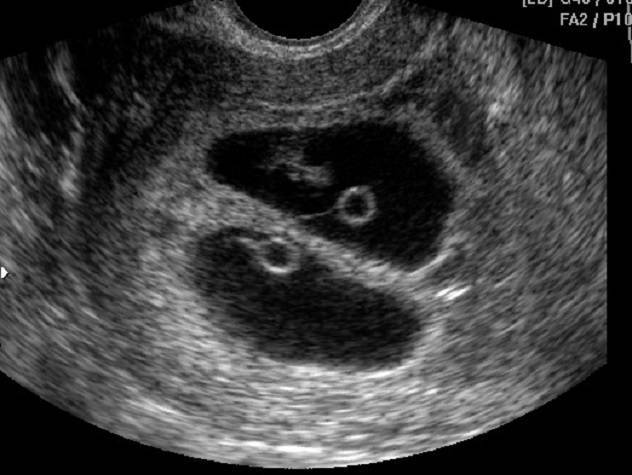

Вообще, плодное яйцо является самым первым признаком нормально текущей беременности. Его можно рассмотреть на ультразвуковом исследовании уже после двух недель задержки менструации. Обычно в данном случае видно плодное яйцо 3-4 недели. Эмбрион же становится заметен только на 5 неделе беременности. Однако если врач диагностирует отсутствие эмбриона в плодном яйце 5 недели– другими словами пустое плодное яйцо, тогда УЗИ через пару недель повторяют вновь.

Обычно в такой ситуации случае на 6-7 неделе плод и его сердцебиение начинают визуализироваться. Когда же плодное яйцо в 7 недель по-прежнему является пустым, это свидетельствует о неразвивающейся беременности